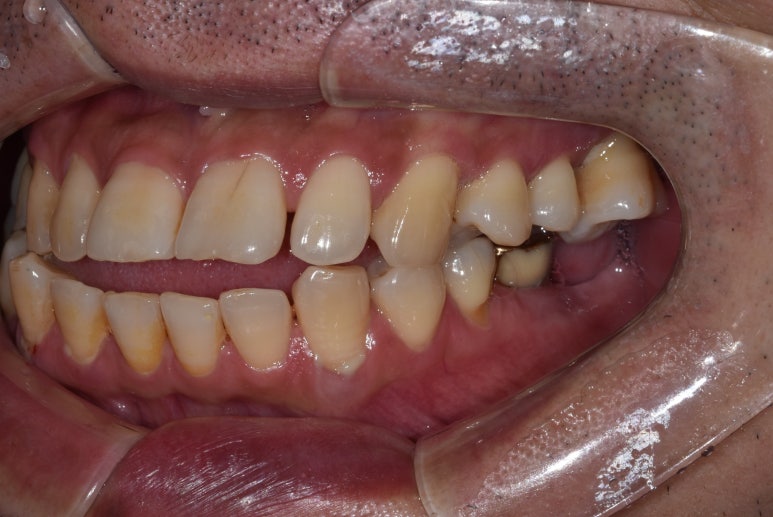

환자분의 첫 내원 시 사진입니다.

거주하고 계시는 동네 치과에서 #25, 26 치아 발치 후 임플란트 치료가 필요하다는 말을 들었는데

저희 디데이치과가 위치한 선릉역 근처에서 근무하고 계셔서 내원해주셨다고 합니다.

우선 살펴보면 임플란트가 필요한 치아는 왼쪽 위 어금니 2개였는데요.

#25 치아는 임플란트를 식립하기에 잇몸뼈의 양이 부족하고 뼈의 상태도 좋지 않아

뼈이식을 진행한 후 잇몸뼈가 단단하게 자리잡힐 때까지 기다렸다가 임플란트를 식립하는

지연식립이 필요한 것으로 진단했습니다.

옆에 있는 #26 치아는 염증이 심해 잇몸뼈가 상당히 녹아 치아 뿌리 일부가 노출되어 있는 상태였습니다.

하루 빨리 발치 후 임플란트를 식립해야 하는 상태였는데,

상악동이라고 하는 공기주머니가 많이 내려와 있어 이를 올려주는 상악동거상술까지 진행해야 하는 것으로 진단했습니다.

뼈이식과 상악동거상술까지 동반한 케이스라 발치한 당일 임플란트 식립은 어려워

일단 내원 당일 발치와 뼈이식까지만 진행하고 약 3개월 후 임플란트 수술 일자를 잡기로 했습니다.